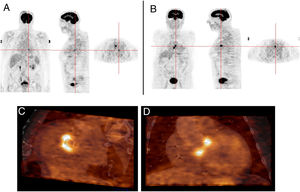

Another advantage of this technique is its ability to detect another infectious focus or even an oncological origin of the IE, revealing pre-malignant or malignant lesions, curative resection of which may be possible if they are discovered at an early stage.7 One patient in our study was referred due to neurological symptoms and was later diagnosed as having had a cerebral stroke following a septic embolism related to IE in a prosthetic aortic valve; this diagnosis was arrived at through 18F-FDG PET. Another patient who underwent 18F-FDG PET for IE had high uptake in the colon, which led to a colonoscopy being performed; adenocarcinoma of the colon was later diagnosed (Figure 5). Another patient in our study population had positive findings on TEE, a vegetation on the native mitral valve, and underwent 18F-FDG PET to exclude septic embolisms; in this patient pathological uptake was found in the native mitral and the prosthetic aortic valve (Figure 6).

Infective endocarditis in a mechanical aortic valve in a 77-year-old male with a mechanical aortic valve, referred after two weeks of fever and back pain. He presented blood cultures positive for Streptococcus bovis. Transesophageal echocardiography and prospective ECG-gated cardiac CT results were negative for endocarditis. 18F-FDG P ET study revealed hypermetabolism in the aortic valve annulus (SUVmax 2.8) (A and B) and in the lumbar column at L3-L4 level (SUVmax 6.3) (C), and radiopharmaceutical uptake is visible in the descending colon at the splenic angle (SUVmax 7.9) (D). A colonoscopy with biopsy was performed, resulting in the detection of adenocarcinoma of the colon.

Infective endocarditis in the native mitral valve and bioprosthetic aortic valve in an 88-year-old male hospitalized due to persistent fever and blood cultures positive for Streptococcus viridans. Echocardiographic results show a vegetation on the native mitral valve and no alterations in the bioprosthetic aortic valve. 18F-FDG PET images show two positive uptake foci, in (A) the native mitral valve (SUVmax 7.5) and (B–D) the prosthetic aortic valve (SUVmax 5.1).